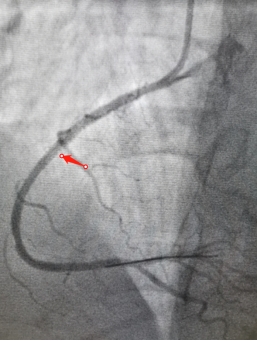

此刻,在手术台的另一边,胸痛中心的张松和赵洪伟两位医生,在高度紧张的氛围下,争分夺秒的为患者进行了冠脉造影检查,结果显示患者为右冠状动脉闭塞,血流完全消失。两位医生当机立断,立刻为患者实施血栓抽吸及球囊扩张术,期间患者又再次反复发作心室颤动,整个身体极度扭曲、不受控制,两位医生凭借过硬的心理素质及娴熟的手术技术,顺利为患者开通了血管并置入一枚支架,整个过程不超过五分钟。随着闭塞血管血流再通,患者逐渐恢复了意识,胸痛症状得到明显缓解,心室颤动波形也随之消失,患者术后安全转入CCU病房监护治疗。

右冠状动脉支架前后对比